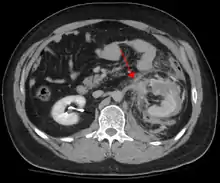

Blunt abdominal trauma

Blunt abdominal trauma (BAT) represents 75% of all blunt trauma and is the most common example of this injury.[4] 75% of BAT occur in motor vehicle accidents,[5] in which rapid deceleration may propel the driver into the steering wheel, dashboard, or seatbelt,[6] causing contusions in less serious cases, or rupture of internal organs from briefly increased intraluminal pressure in the more serious, depending on the force applied. Initially, there may be few indications that serious internal abdominal injury has occurred, making assessment more challenging and requiring a high degree of clinical suspicion.[7]

There are two basic physical mechanisms at play with the potential of injury to intra-abdominal organs: compression and deceleration.[8] The former occurs from a direct blow, such as a punch, or compression against a non-yielding object such as a seat belt or steering column. This force may deform a hollow organ, increasing its intraluminal or internal pressure and possibly lead to rupture.

Deceleration, on the other hand, causes stretching and shearing at the points where mobile contents in the abdomen, like bowel, are anchored. This can cause tearing of the mesentery of the bowel and injury to the blood vessels that travel within the mesentery. Classic examples of these mechanisms are a hepatic tear along the ligamentum teres and injuries to the renal arteries.

When blunt abdominal trauma is complicated by 'internal injury,' the liver and spleen (see blunt splenic trauma) are most frequently involved, followed by the small intestine.[9]